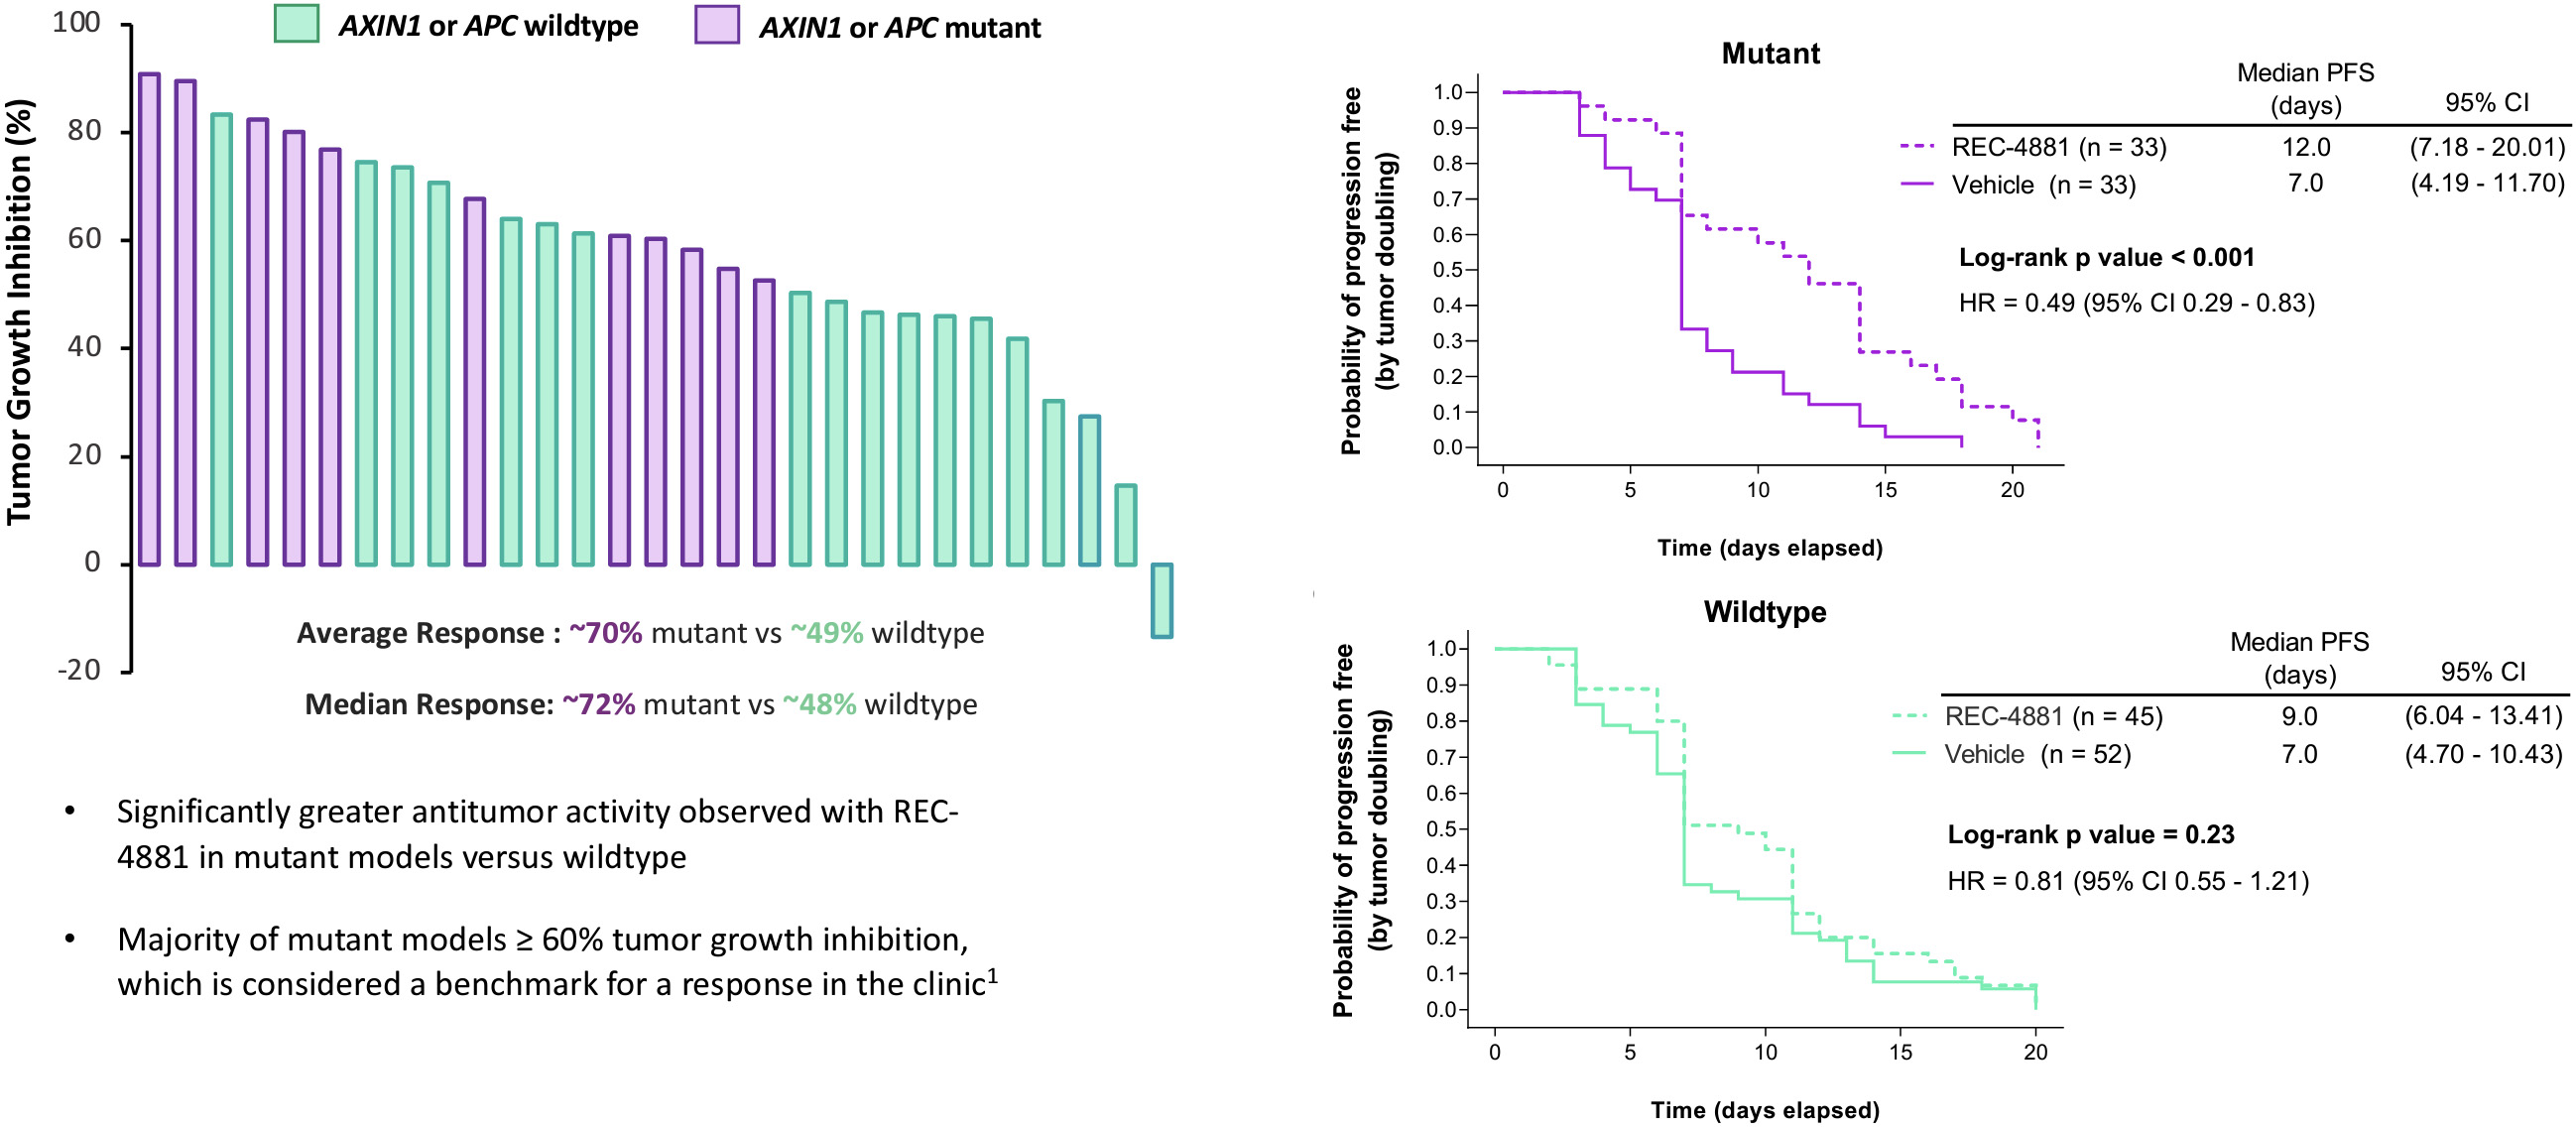

•Five phase 2 clinical-stage programs with multiple upcoming data readouts expected, including REC-994 in cerebral cavernous malformation (CCM) in Q3 2024, REC-2282 in neurofibromatosis type 2 (NF2) in Q4 2024, REC-4881 in familial adenomatous polyposis (FAP) in H1 2025, and REC-4881 in AXIN1 or APC mutant solid tumors in H1 2025